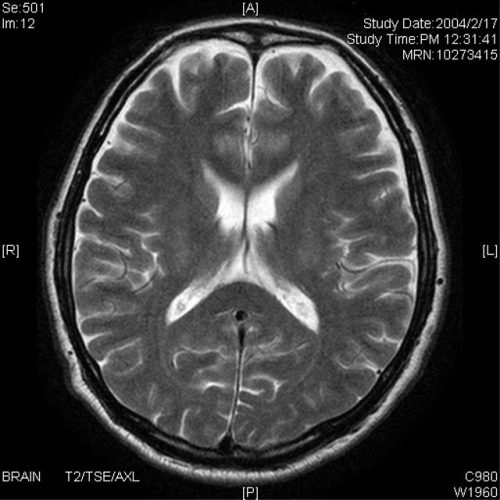

高次脳機能障害の診断基準として、MRI、CT、脳波などで

認知障害の原因と考えられる脳の器質的病変の存在が確認されるか、

あるいは診断書により脳の器質的病変が存在したことが確認できることが

検査所見としてあげられます。